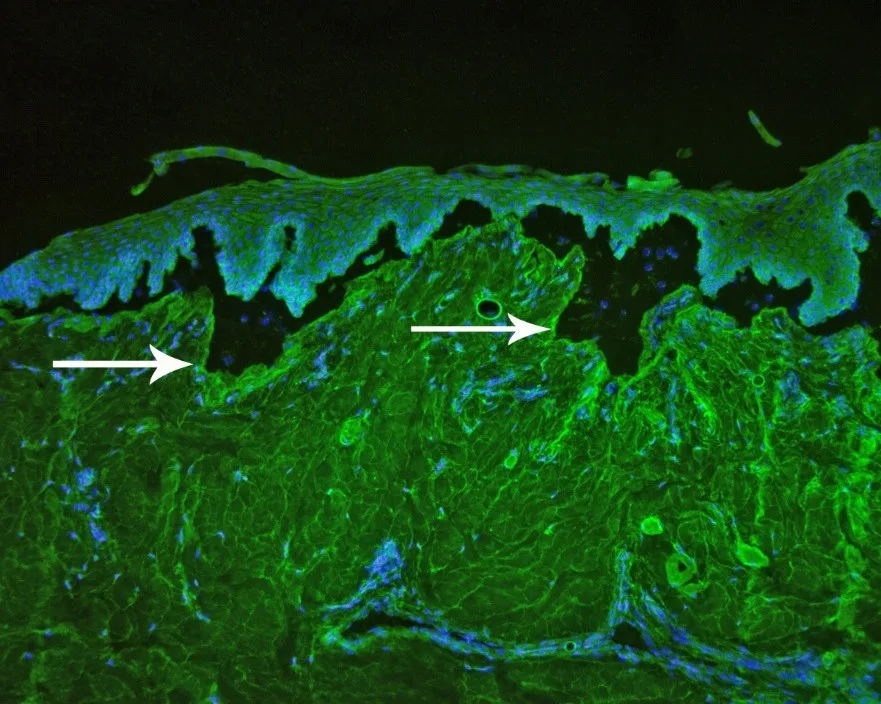

Additional diagnostic tests can be used to definitively diagnose epidermolysis bullosa acquisita.4,5 Circulating autoantibodies to immunoglobulin G can be detected via indirect immunofluorescence assay using salt-split canine buccal mucosal tissue (Figure 9). Autoantibodies targeting the noncollagenous domain of collagen VII can be confirmed in most tested dogs via immunoblotting (Figure 10), ELISA with human recombinant proteins, or canine noncollagenous-transfected 293 T cells.

FIGURE 9 Indirect immunofluorescence assay showing immunoglobulin G autoantibodies targeting the dermal side of salt-split canine skin (arrows). Magnification ×10. Image courtesy of T. Olivry, North Carolina State University.

FIGURE 10 Indirect immunofluorescence examination, using human embryonic kidney cells, transfected with the aminoterminal noncollagenous domain of type VII collagen showing positive fluorescence (arrows). Magnification ×20. Image courtesy of T. Olivry, North Carolina State University.